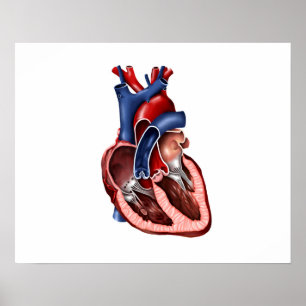

Poster 1833 interno da anatomia do coração do

Preço36,00 €